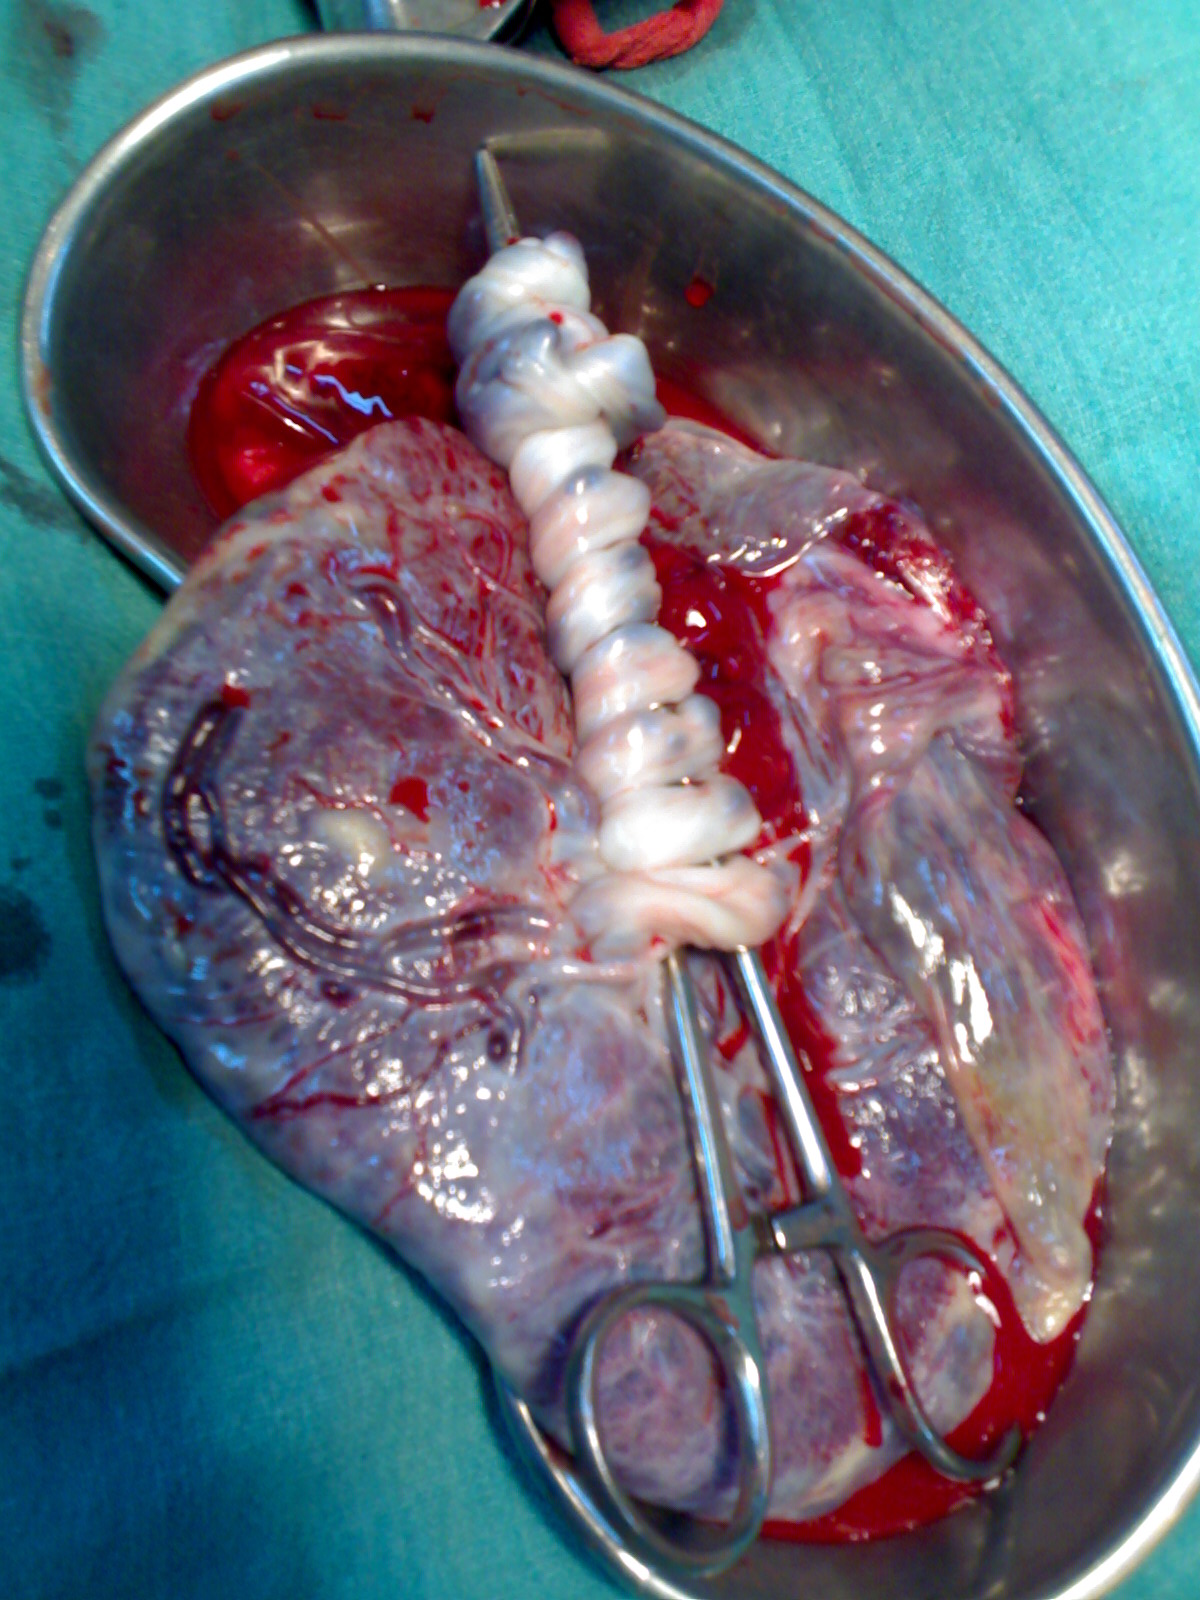

탯줄은 태아와 태반을 연결하는 기관으로, 출생 시 굵기 2cm, 길이 50~60cm 정도이다. 탯줄에는 2개의 제대 동맥과 1개의 제대 정맥이 있으며, 이 혈관 속 혈액이 제대혈이다.[49] 제대혈은 출산 후 태반이나 탯줄에 남아있는 혈액을 채취하여 보존한 것이다.[51][52] 이전에는 폐기되었으나, 1980년대 초반 조혈 줄기 세포가 포함되어 있다는 사실이 밝혀졌다. 1988년에는 제대혈을 사용한 최초의 이식(Fanconi 빈혈 아동 대상)이 이루어졌고,[53] 이후 각국에서 제대혈 은행이 설립되어 백혈병 등 질환 치료에 활용되고 있다.

출산 후 탯줄은 신생아에게서 절단되고 태반도 배출되므로, 탯줄에서 혈액을 채취해도 신생아나 산모에게는 영향이 없다.[54]

제대혈은 아기가 태어난 후 태반과 탯줄에 남아 있는 혈액이다. 제대혈 채취는 일반적으로 "밀폐 기술"을 사용하여 이루어진다.[13] 이 방법은 표준 혈액 채취 기술과 유사하며, 기술자는 혈액 백에 연결된 바늘을 사용하여 절단된 탯줄의 정맥에 캐뉼라를 삽입하고, 제대혈은 바늘을 통해 백으로 흘러 들어간다. 평균적으로 약 75ml의 제대혈을 채취할 수 있다.[14]

출산 후 탯줄은 신생아로부터 절단되고, 태반도 곧 배출(후산)된다. 신생아로부터 절단된 후의 탯줄로부터 혈액을 채취해도 신생아나 모체에는 아무런 영향이 없다.[54]

채취된 제대혈은 저온 보존되어 제대혈 은행에 보관된다.[15] 제대혈 채취 후에는 줄기 세포 회수율을 높이기 위해 적혈구를 제거하는 등, 이식에 필요한 세포만 남기는 처리 과정을 거친다. 채취된 제대혈에는 조혈모세포 외에도 적혈구, 백혈구, 혈소판, 혈장 등이 포함되어 있는데, 적혈구 등은 이식에 불필요하며 액체 질소 탱크의 공간을 효율적으로 사용하기 위해 제거한다.